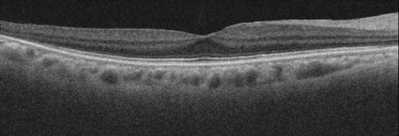

眼の中には硝子体という、水晶体と網膜の間の空間を満たすゼリー状の物質でが存在します。加齢とともに硝子体が液体に変化し網膜から剥がれます。(後部硝子体剥離)(図1)後部硝子体剥離が起こったとき、硝子体と黄斑の癒着が強いとうまくはがれず、黄斑に残った硝子体を基にして、黄斑前膜ができます。(図2)